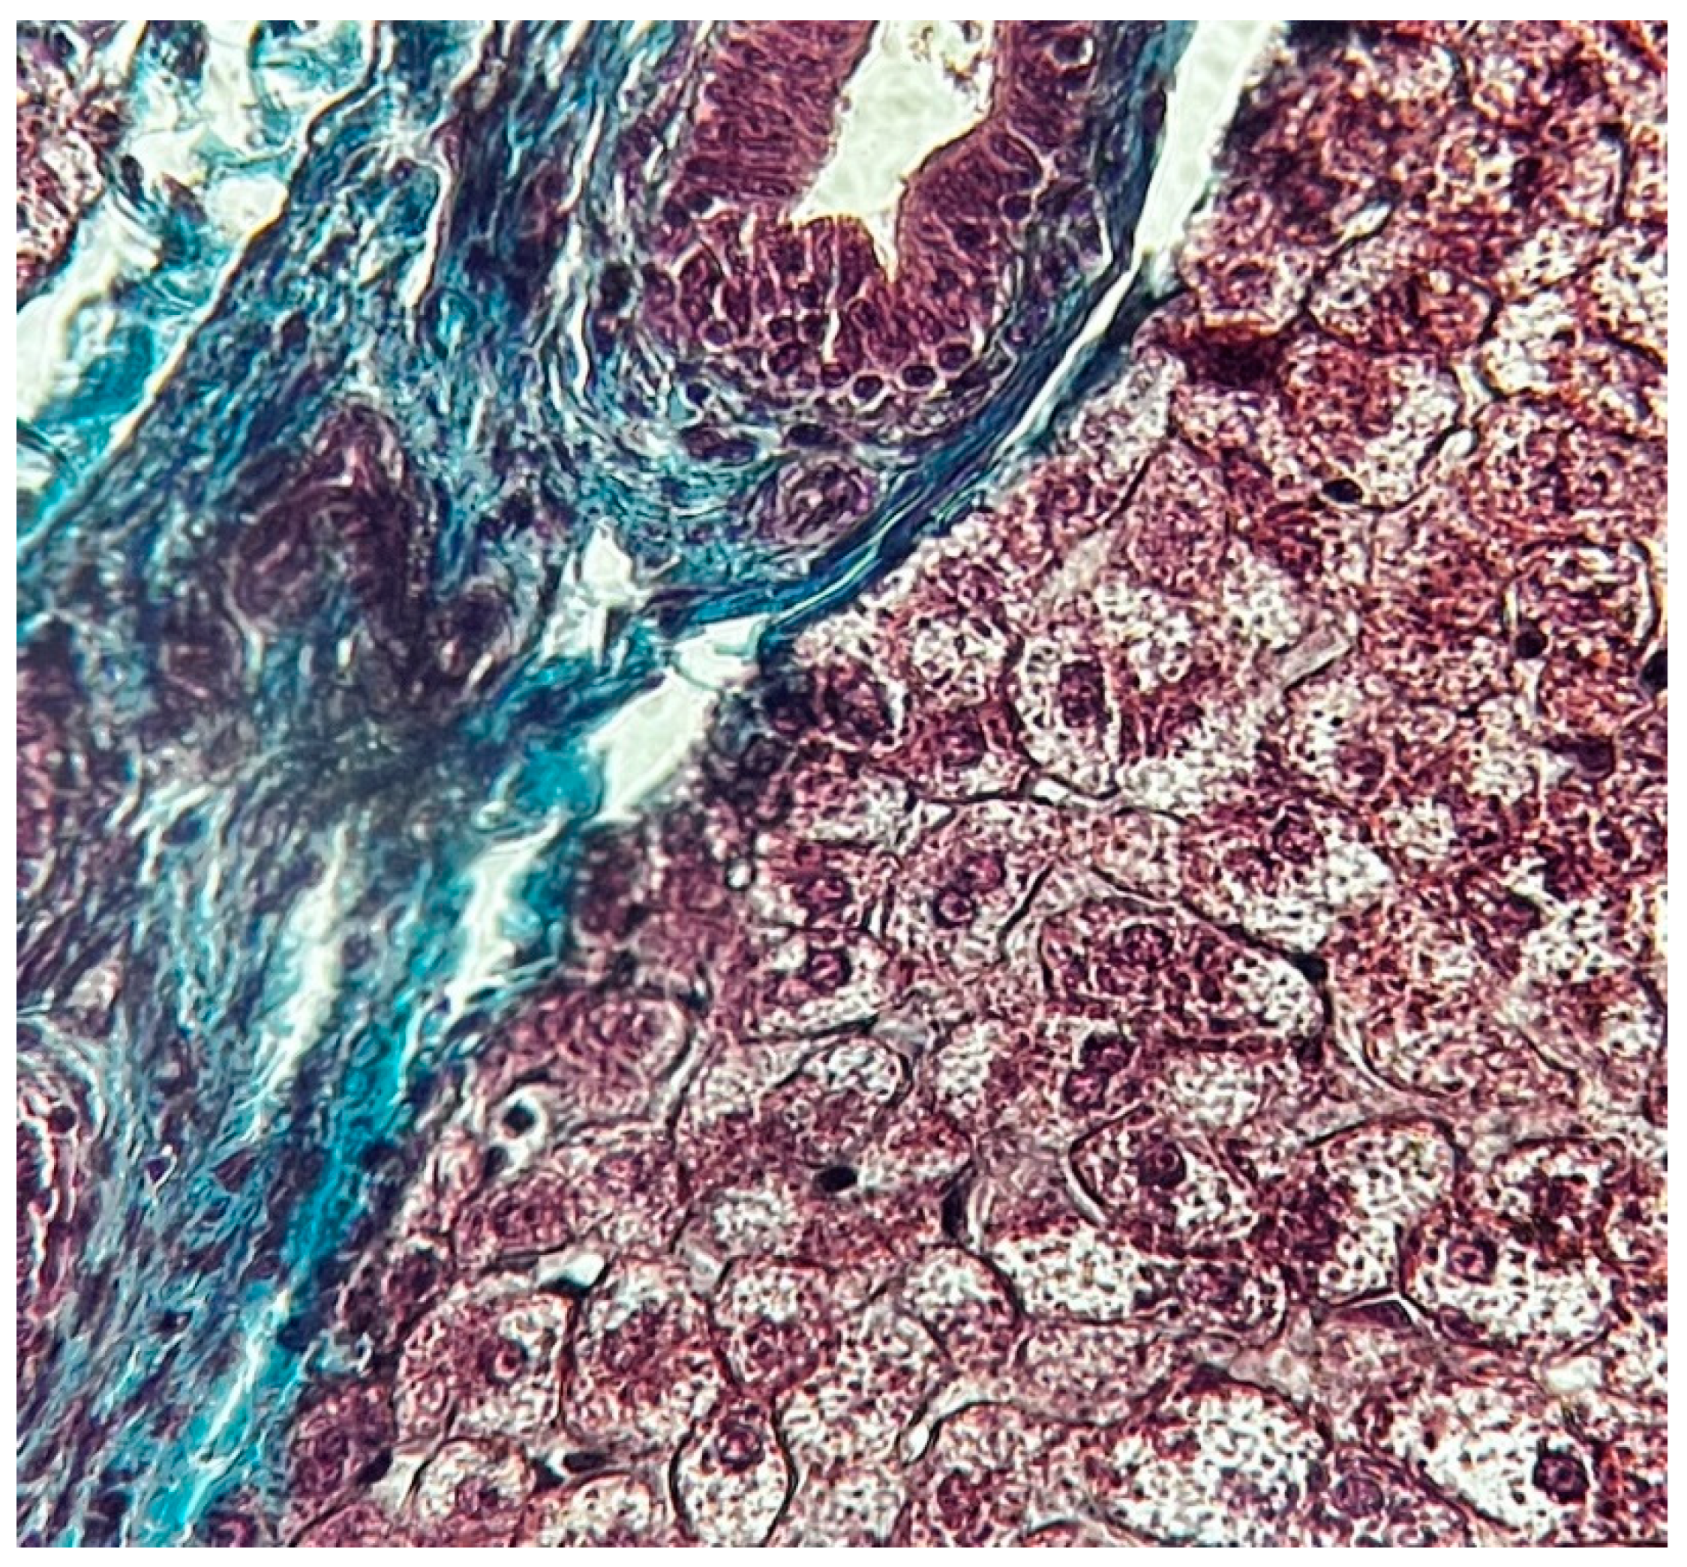

The functional unit of the liver is the lobule with hexagonal form. Kienann space is specific for liver strucutre, including a portal triad (portal vein, hepatic artery, bile duct) sits at each corner of the hexagon. Mitochondri as points observing with lens x40. Portal vein with enlarge lumen (Figure 1).

Figure 1. Normal liver x 40 Goldner Szekely stain.

Figure 2. Normal liver x10 Goldner Szekely stain.